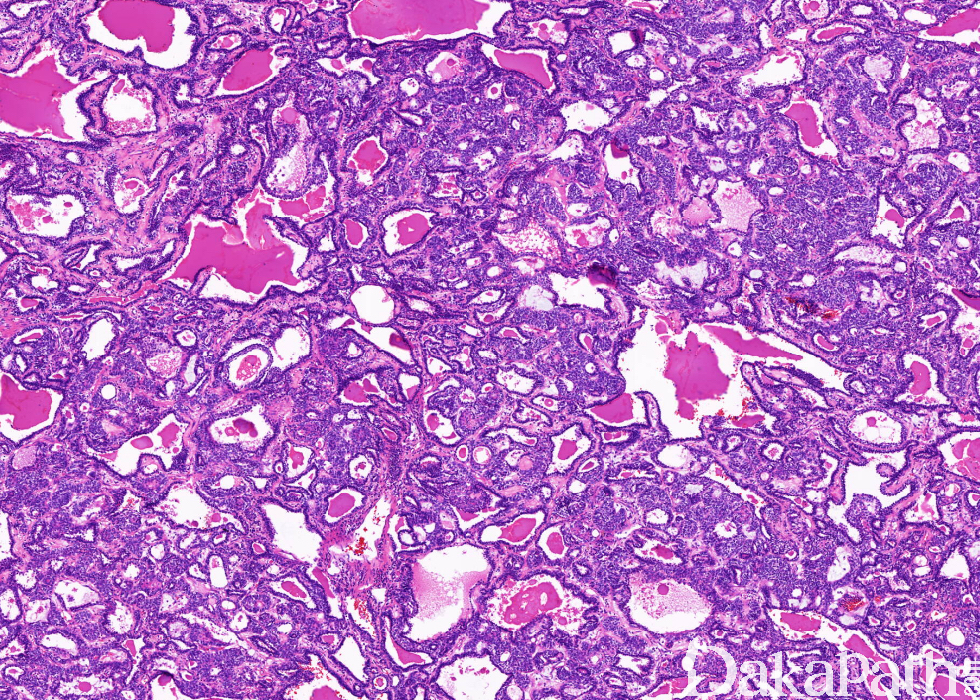

是一种低度恶性上皮性肿瘤,具有双向分化,由管状结构的内层上皮细胞和外层的梭形、透明细胞样或浆细胞样肌上皮组成。

发病年龄范围在 30 ~ 71 岁之间,表现为支气管内质地均一、界限清楚的实性肿瘤,切面灰白-褐色,可伴黏液样外观;

由两种细胞不同比例混合组成管状结构,偶可形成实性细胞巢;

肿瘤细胞可浸润周围肺实质。